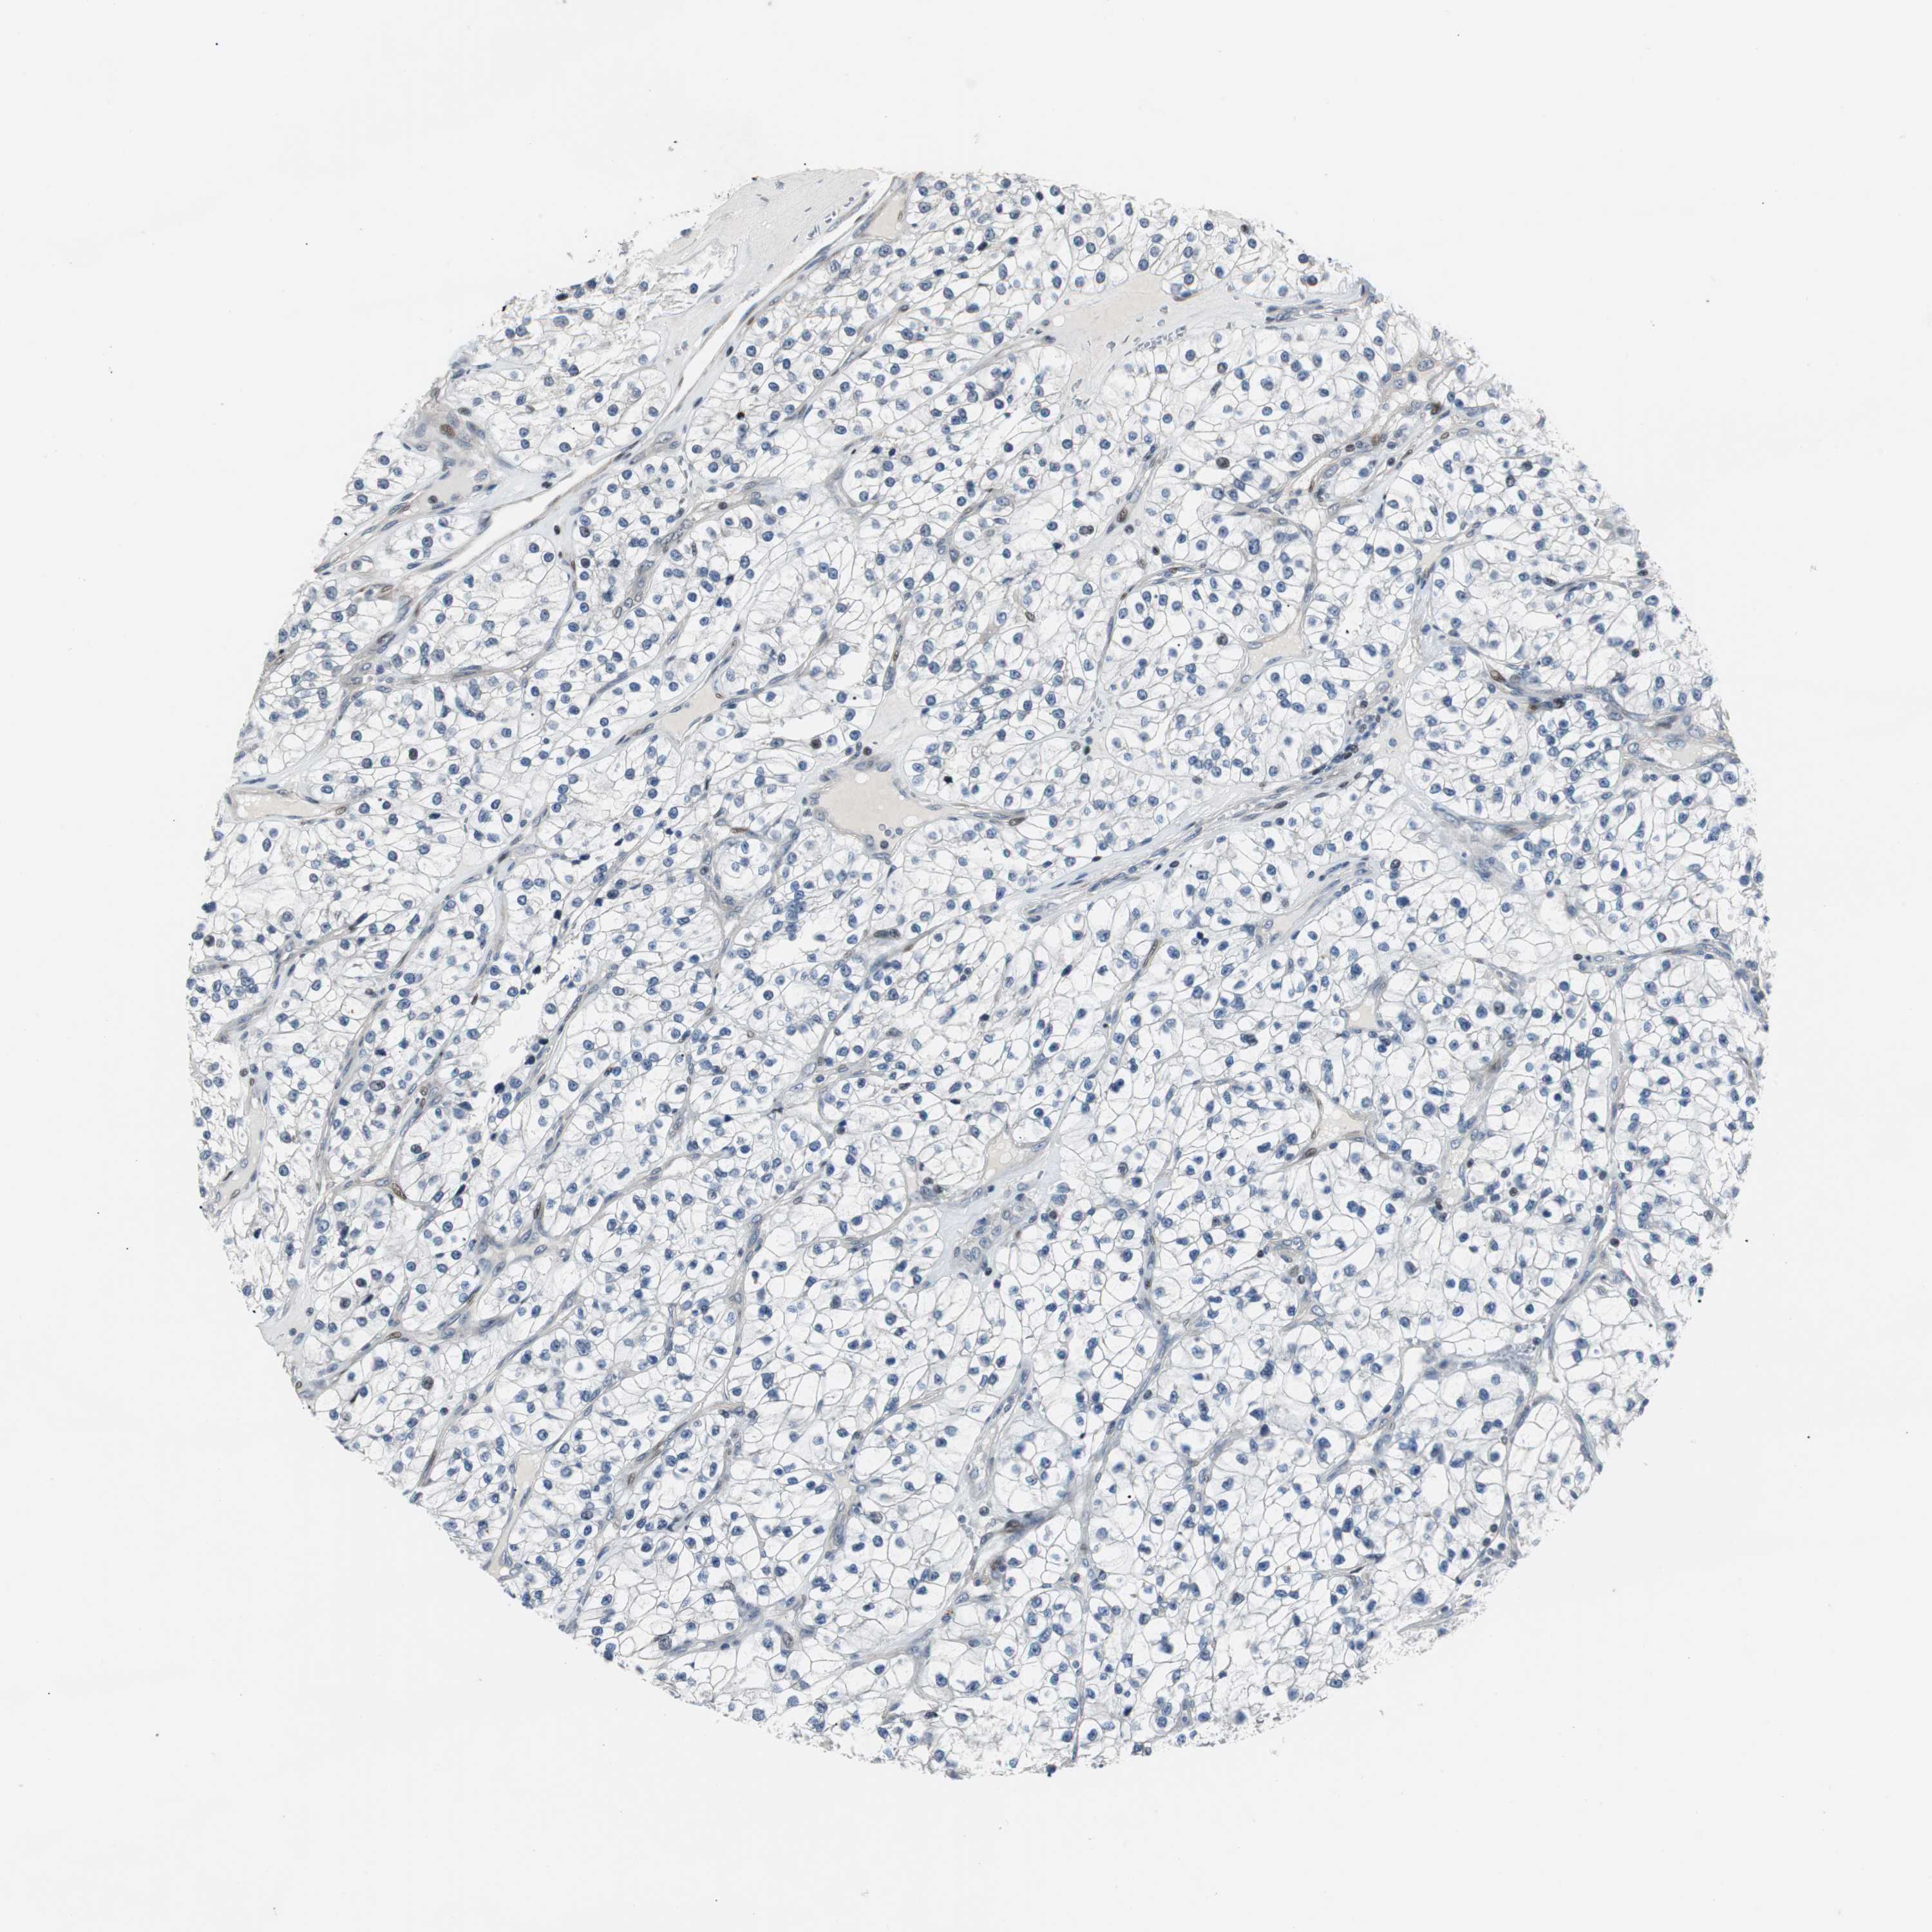

CANCER RENAL CANCER Show tissue menu

KICH TCGA KIRC TCGA KIRC VALIDATION KIRP TCGA PROTEIN RCC CPTAC PROTEIN EXPRESSION

KIDNEY CHROMOPHOBE (TCGA) - Interactive survival scatter ploti

The Survival Scatter plot shows the clinical status (i.e. dead or alive) for all individuals in the patient cohort, based on the same data that underlies the corresponding Kaplan-Meier plots. Patients that are alive at last time for follow-up are shown in blue and patients who have died during the study are shown in red.

The x-axis shows the expression levels (FPKM) of the investigated gene in the tumor tissue at the time of diagnosis. The y-axis shows the follow-up time after diagnosis (years). Both axes are complimented with kernel density curves demonstrating the data density over the axes. The top density plot shows the expression levels (FPKM) distribution among dead (red) and alive patients (blue). The right density plot shows the data density of the survived years of dead patients with high and low expression levels respectively, stratified using the cutoff indicated by the vertical dashed line through the Survival Scatter plot. This cutoff is automatically defined based on the FPKM cutoff that minimizes the p-score. The cutoff can be changed by dragging the vertical line or by entering a cutoff value in the square labeled "Current cut-off".

Under the Survival Scatter plot the p-score landscape (black curve; left axis) is shown together with dead median separation (red curve; right axis). Dead median separation is the difference in median mRNA expression between patients who have died with high and low expression, respectively. It is calculated as follows: median FPKM expression of dead patients with high expression - median FPKM expression of dead patients with low expression. This is intended to aid the user in visually exploring custom cutoffs and the associated p-scores and dead median separation.

Individual patient data is displayed and can be filtered by clicking on one or more of the category buttons on the top of the page. Categories describing expression level and patient information include: high, low, alive, dead, female, male and tumor stages. The scale of the x-axis can be toggled between linear and log-scale by clicking on the "x log" button. Mouse-over function shows TCGA ID, patient information and mRNA expression (FPKM) for each patient.

& Survival analysisi

Kaplan-Meier plots summarize results from analysis of correlation between mRNA expression level and patient survival. Patients were divided based on level of expression into one of the two groups "low" (under cut off) or "high" (over cut off). X-axis shows time for survival (years) and y-axis shows the probability of survival, where 1.0 corresponds to 100 percent.

RAD1 is not prognostic in Kidney Chromophobe (TCGA)